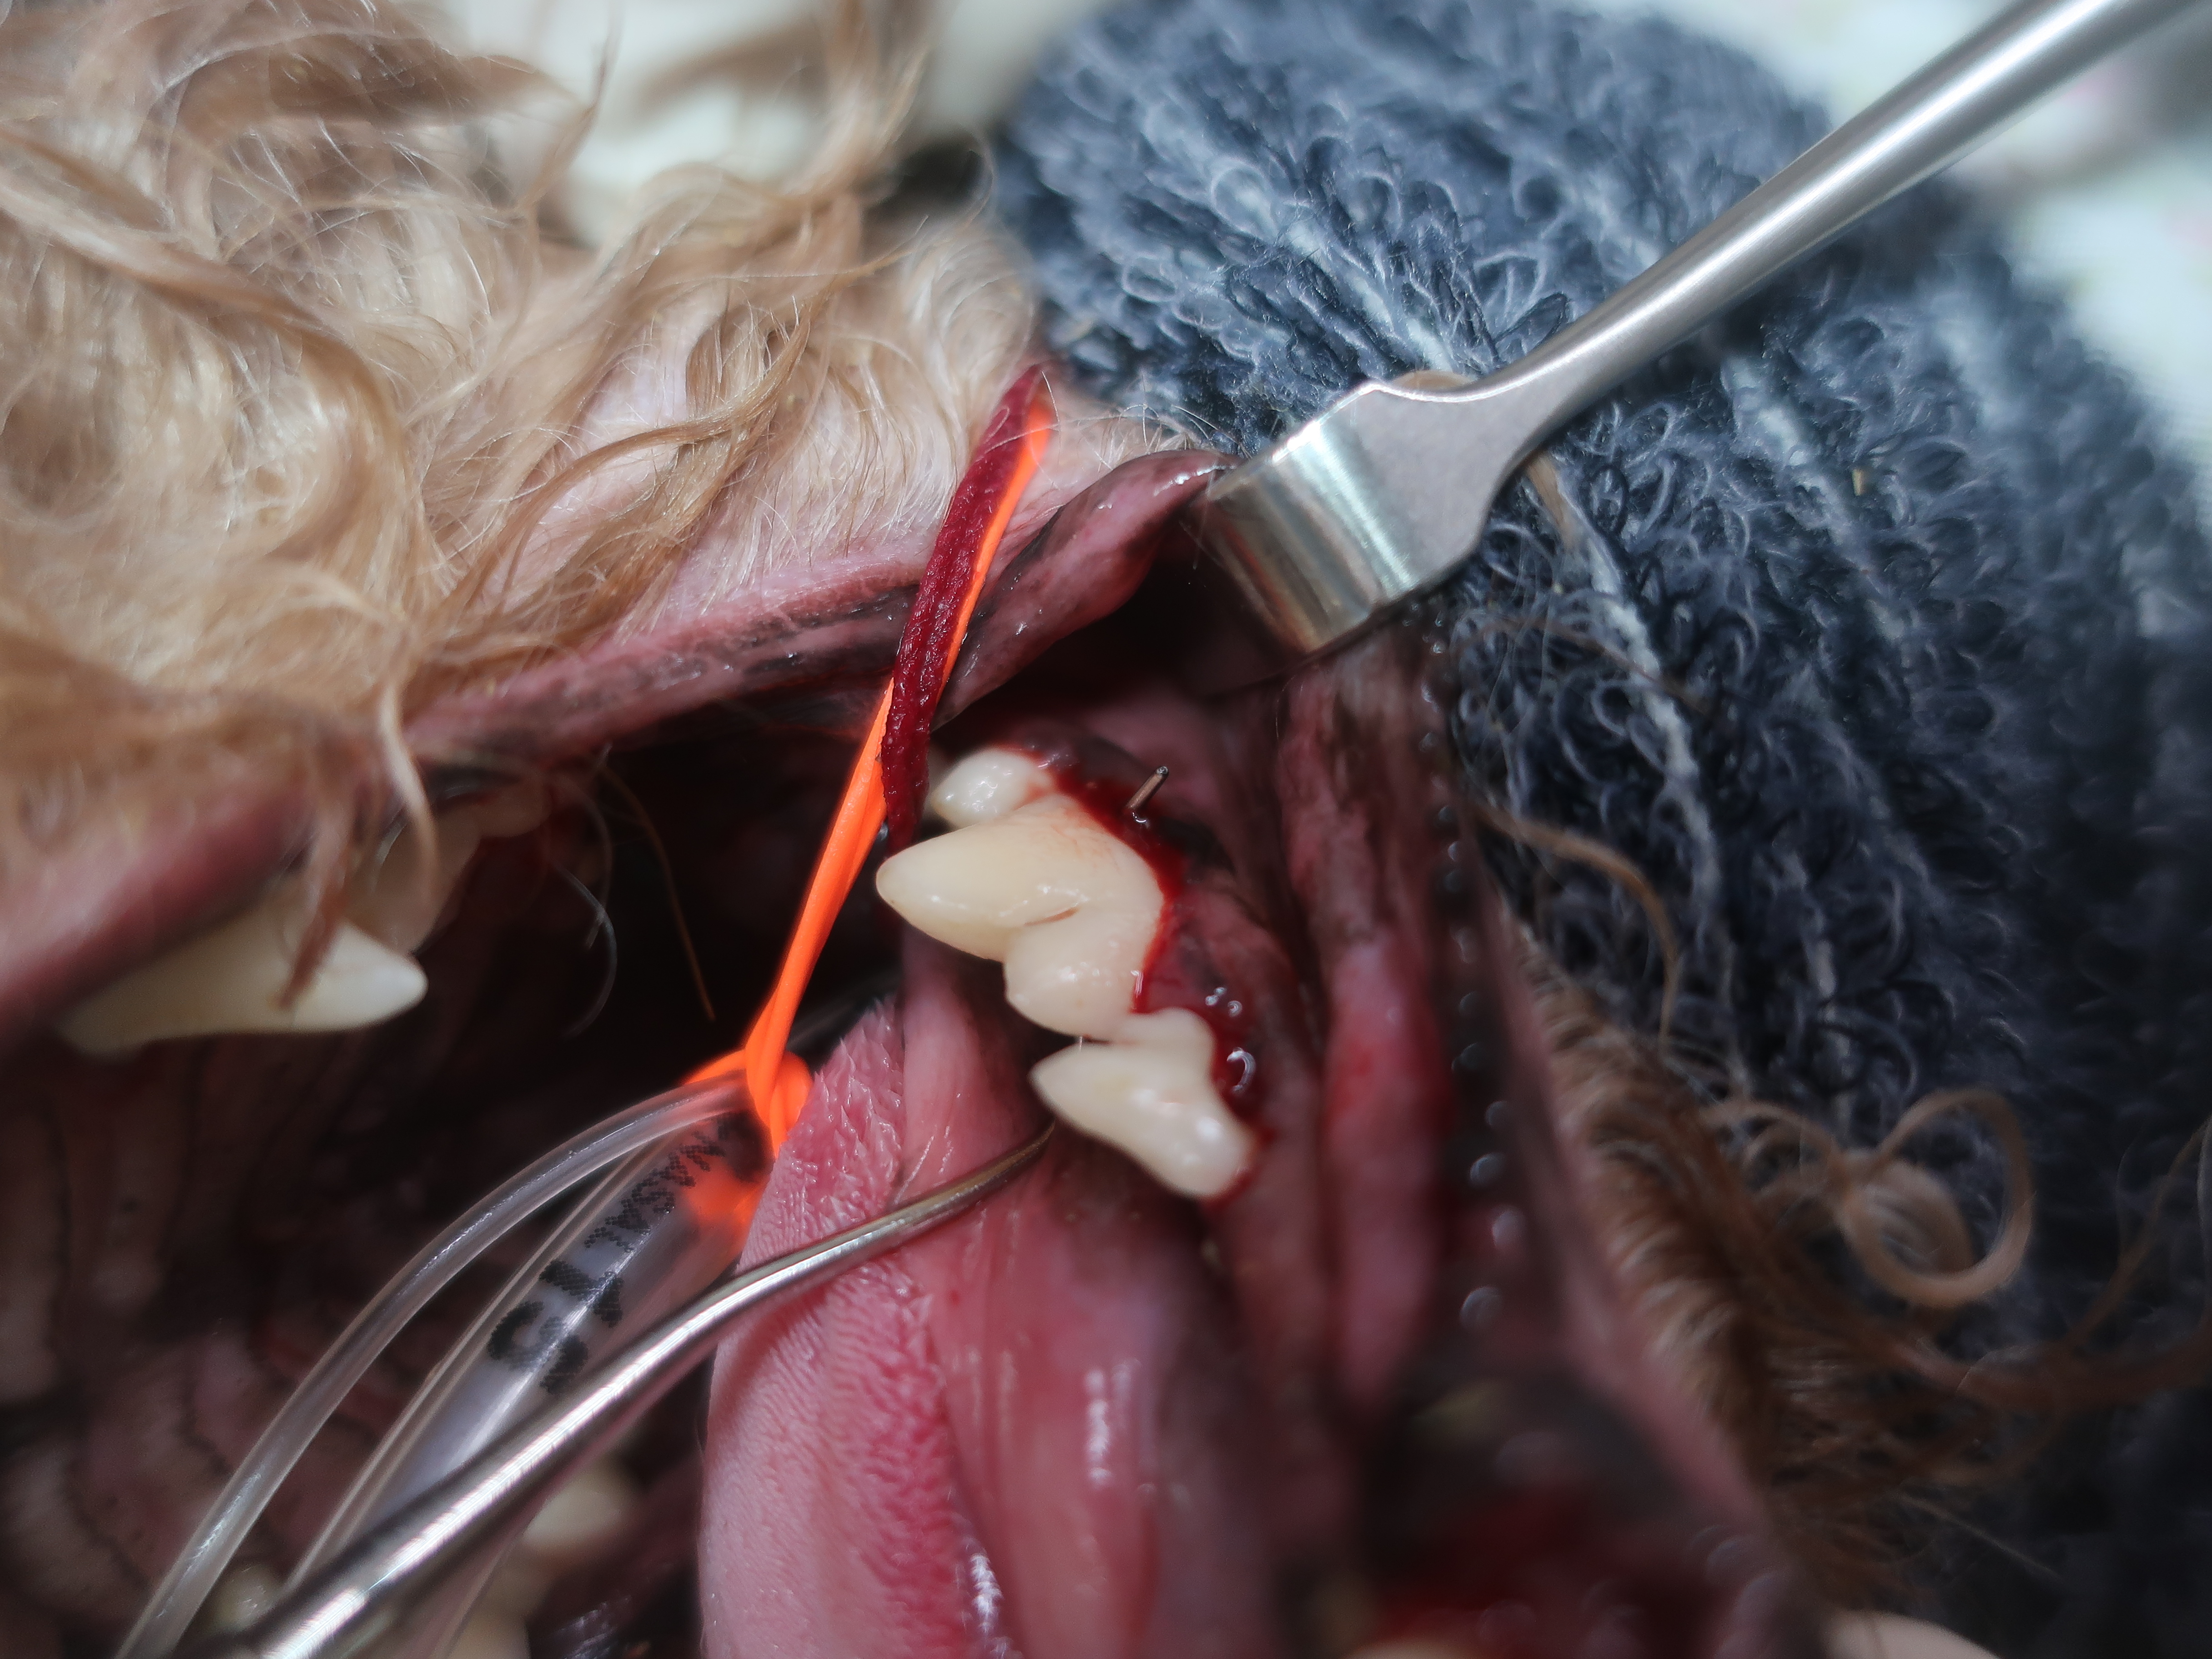

根分岐部病変(歯周病が進み歯槽骨が溶けてしまい歯根部が露出している状態)も見られました。

左下顎第4前臼歯は歯根部がトンネルのようになっており、プローブが貫通しています。